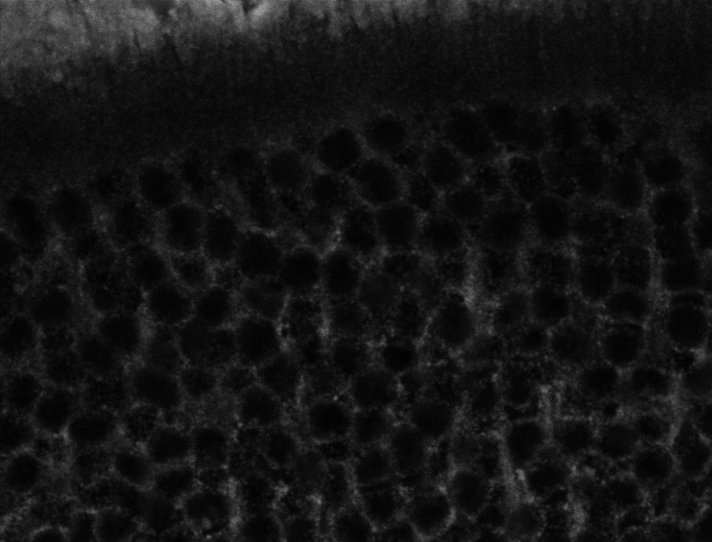

Nuclei

Nuclei - Bis